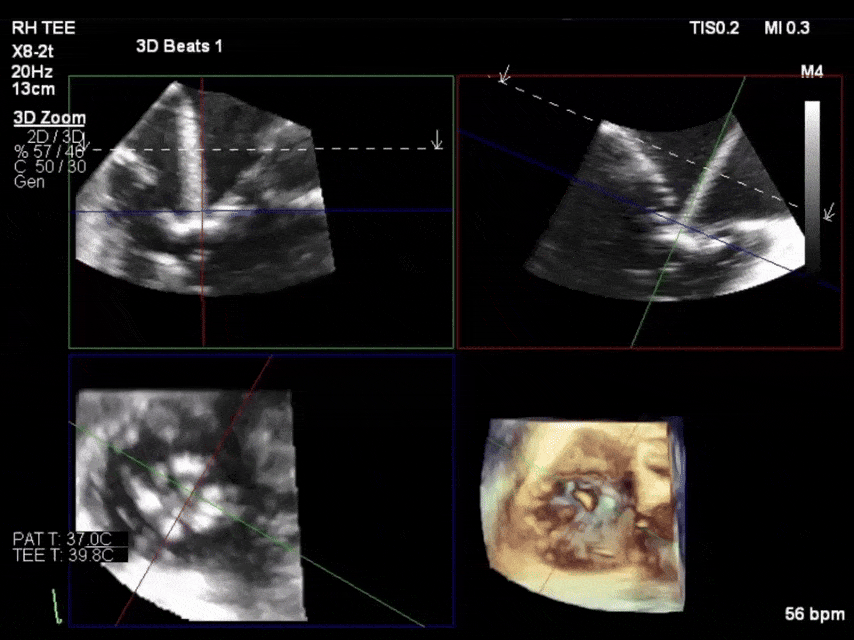

69岁女性,既往有房颤病史、4年前接受A型主动脉夹层修复术,3年前因重度二尖瓣反流(MR)及三尖瓣反流(TR)行经导管缘对缘修复术(TEER),此次因心衰管理问题就诊寻求第二诊疗意见。

二尖瓣修复效果持久稳定,但TR因发生单侧瓣叶装置附着(SLDA)于术后短期内复发为极重度反流。尽管强化药物治疗,症状仍持续恶化,遂考虑TR再次干预。

虽患者相对年轻,但心脏团队评估认为其因既往手术史及衰弱状态属外科高危。经导管方案中,因存在较大对合间隙及原发性瓣叶退变,再次TEER不可行,故TTVR成为唯一选择。前叶脱落的夹子对依赖瓣叶锚定的EVOQUE瓣膜植入构成挑战——该夹子可能阻碍锚定件进入瓣叶后方并影响成像。但由于脱落夹子靠近前隔联合处,研判其可为输送系统操作及瓣膜释放保留中央区足够空间。术中对锚定件与TEER装置的相对位置进行精确定位评估,最终锚定件分列装置两侧无空间冲突,且无瓣周漏。1年随访时患者自述"重获新生",未再出现心衰症状。

TEER是目前研究最深入、技术最成熟的TR经导管治疗方案,但中度以上残余TR被证实是预后不良的强预测因子。因此决策时需评估能否实现充分TR减轻。TTVR的优势在于可使90%以上患者术后TR降至轻度以下。本案例证明TTVR可作为TEER后显著残余TR的补救方案,但需精细解剖评估。我们认为存在多个TEER装置或非联合部定位是TTVR的两大潜在限制因素。本例因单侧瓣叶装置附着使器械向心室侧移位,反而使TTVR瓣膜能在原生瓣环实现完美密封而无显著瓣周漏。随着经验积累,这类手术可安全实施,但必须在高度专业化中心进行评估以确保成功率。